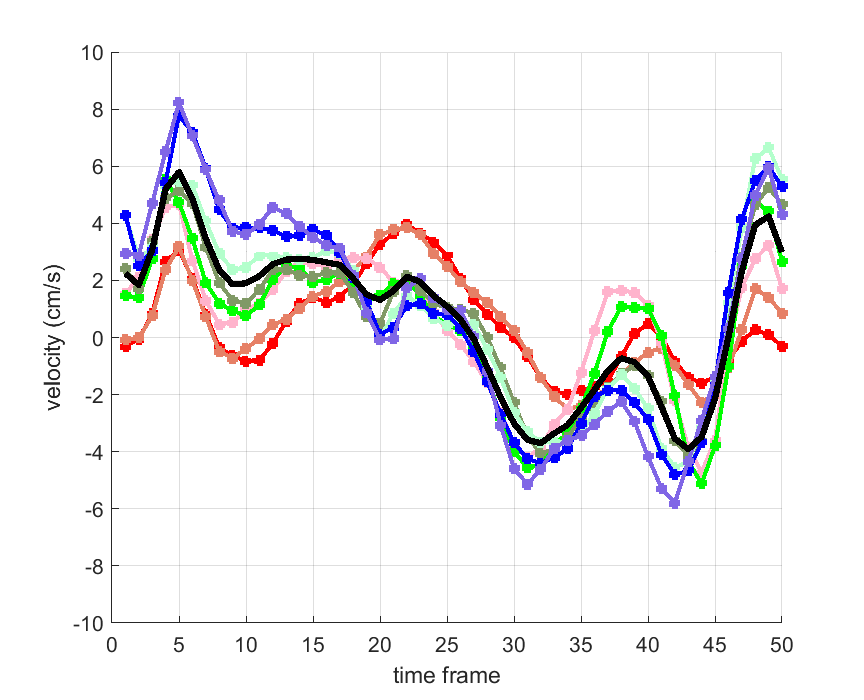

Time courses of the estimated translational component per subject, frame, slice and volume along the 3 velocity directions x, y and z are presented in Fig.6 - Fig.8.